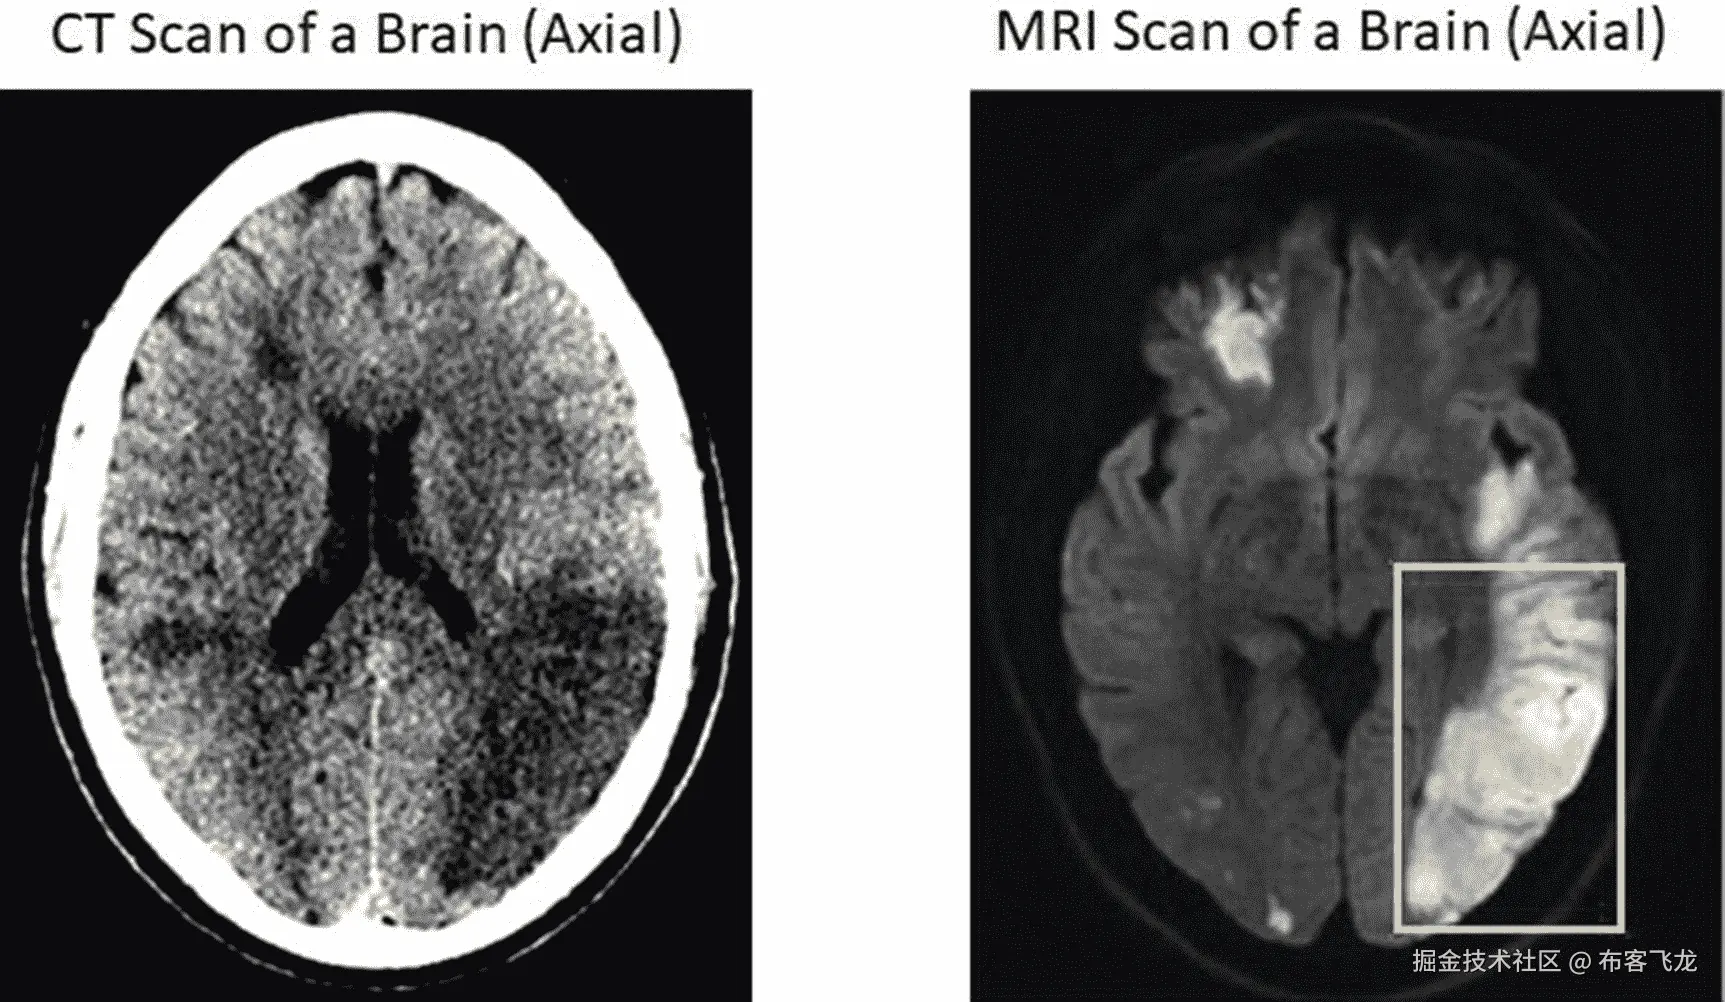

img/502837_1_En_8_Fig3_HTML.jpg

图 8-3

核磁共振扫描比 CT 更清楚地显示受伤的脑组织

• 提高发现问题的敏感性(异物/血管问题等)。)

• 与像 X 射线这样的 2-D 成像模态相比,3-D 成像模态允许更好的定位。

• 更好地描绘组织类型。例如,如图 8-3 所示,如果目标是发现中风中受伤的脑组织,您可以看到,与 CT 相比,MRI 图像清楚地显示了受损区域,而 CT 的大部分区域是黑暗的。